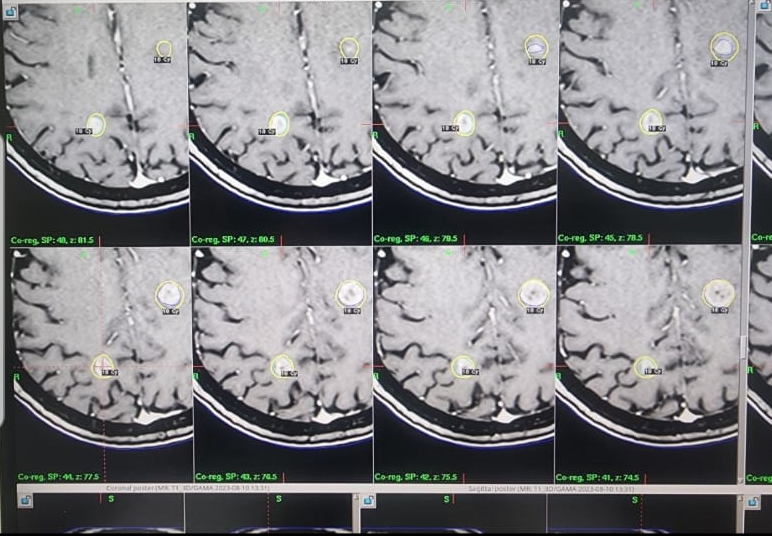

• Professor Dr. Abdul Ameer Jasim Mohammed, a faculty member in the Department of Surgery at Al-Nahrain College of Medicine, provided a medical service using the Icon Gamma Knife technique for the first patient to be treated with this technique. This is the first time in the history of treatment, and it was done in the presence of a group of specialists.

. A widespread brain tumor was treated with gamma rays, resulting in the tumor disappearing in an extraordinary manner. The case was followed up in 2024.